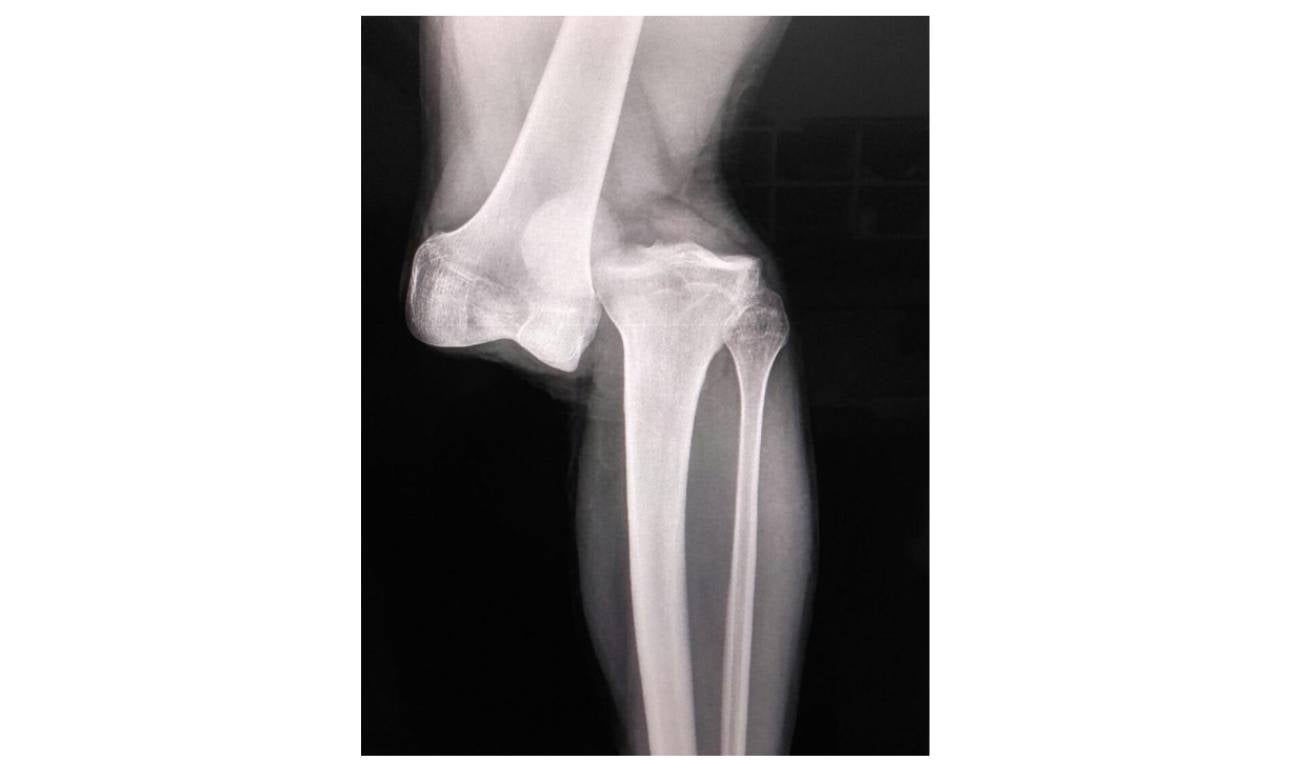

La imagen que se conoce de la radiografía resultó ser aterradora para los amantes del fútbol que han lamentado la mala suerte de Luciano Sánchez.

Luego de haber salido con la impactante lesión, se conoció esa imagen que puso a sudar frío a más de uno.

El propio médico de Argentinos Juniors dijo que en más de dos décadas de carrera jamás había visto una lesión semejante.

Es casi que completa la separación del fémur y el peroné, una lesión que dejará fuera de las canchas por al menos seis meses a Luciano Sánchez.

“En 23 años como médico nunca vi una lesión así. Es casi una separación del fémur y el peroné. Hay rotura de cruzado, anterior, posterior... Hay que hacer una reconstrucción. La recuperación es de entre 10 y 12 meses”, señaló Alejandro Ronconi, médico de Argentinos Juniors.